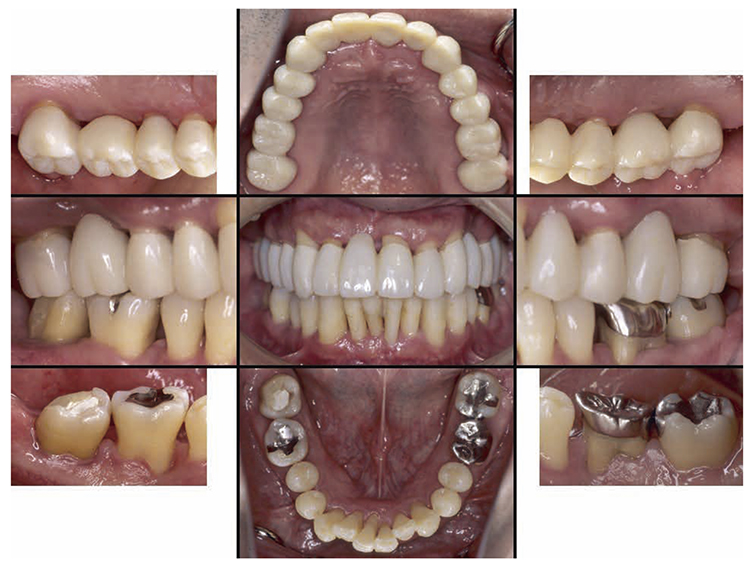

No obvious redness and swelling were present in the marginal gingiva across the full jaw; some blood congestion was however observed. The gingival shape of the anterior teeth in the mandible and maxilla was that of a thick shelf. Significant gingival recession was observed on the mandibular anterior teeth and the buckle side of the left and right maxillary first molar. The dental arch on the maxilla and mandible had a parabolic shape. Teeth separation was however observed between the maxillary central incisors, maxillary right central incisor and lateral incisor, maxillary right canine and first premolar, maxillary left canine and first premolar, and crowding was observed in the mandibular central incisors (Fig.1a).

At the time of first visit, the average PD (Probing Depth) on the full jaw was 4.5mm,maximum PD was 10.0mm, 43.5% had PD of 3mm or less,38.7% for 4-6mm,17.9% for 7mm or above. The average BOP (Bleeding on Probing) on the full jaw was 42.3%,teeth mobility on 17,22,23,32,33,41,46 was grade 1,grade 2 on 11,12,21,and grade 3 on 16,24,26,31 (Miller classification). Additionally, grade 1 on 36,16(mesial, distal),26 (mesial, distal) and 36,grade 2 furcation involvement (Lindhe & Nyman classification) was observed on 47. The plaque score at the first visit (O’Leary’s Plaque Control Record:PCR value) was 83.9%, which indicated poor oral hygiene status (Fig.1b).

At the first visit, the findings showed moderate to advanced horizontal alveolar bone resorption in the entire jaw, and advanced vertical bone resorption on 24,36,46, 47. Additionally, on 46,47 were radiolucent findings that were likely associated with furcation involvement, and radiolucent areas on the alveolar bone surrounding the root apex were shown on 16,11,26. Furthermore, distally on 47, radiolucent findings showed caries extending into the dental pulp.(Fig.1c).

Fig 1a

(Fig.1a) Intraoral photo taken during first visit (June 2007)

Fig 1b

(Fig.1b) Results of periodontal tissue examination during first visit (June 2007)

Fig 1c

(Fig.1c) Dental X-ray 14 during first visit (June 2007)